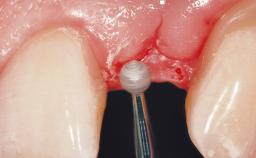

A 33-year-old female patient presented with an upper left central incisor that required extraction after a failed endodontic therapy. The tooth had been traumatized when the patient was a teenager and had undergone several endodontic treatments, including two apicectomy procedures. The patient was in good health and did not smoke. Clinical examination showed that the patient had a high lip line. In full smile, the gingival margins of the upper teeth were visible to the first molars. The gingival margins of central incisors 11 and 21 were only just showing. Examination of tooth 21 confirmed that the tooth was mobile and had hypererupted by 1 mm.

Soft Tissue Grafting Simultaneous

Soft Tissue Contour and Volume Slightly compromised